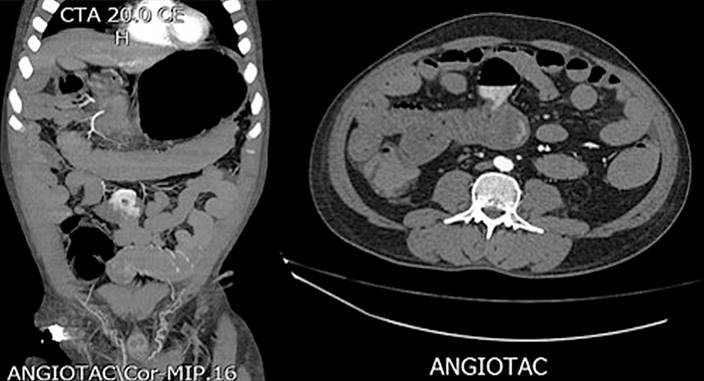

La angiotomografía abdominal se considera el método diagnóstico de primera línea en un paciente con sospecha de sangrado procedente del intestino delgado, debido a que permite visualizar la presencia o ausencia de extravasación del material de contraste en la luz intestinal; tiene una sensibilidad del 86% y especificidad del 95% para el diagnóstico de hemorragia digestiva aguda20.

Durante los tres primeros días de hospitalización persistió con hematoquecia, hipotensión y anemización grave que no corrigió a pesar de ser politransfundido, por lo que se solicitó arteriografía mesentérica, en la cual no se encontraron lesiones que explicaran el sangrado. El paciente se tornó inestable hemodinámicamente, por lo que fue trasladado a la unidad de cuidados intensivos (UCI) con requerimiento transfusional, soporte vasopresor y ventilación mecánica invasiva. Además, tenía un cuadro de hematemesis con necesidad de endoscopia de vías digestivas altas que reportó una “angiodisplasia de bulbo duodenal, la cual recibió escleroterapia”. Por la persistencia de inestabilidad hemodinámica, sangrado digestivo bajo y anemización grave, se realizó una angiotomografía abdominal, en la que se observó una “dilatación en el segmento intestinal delgado ileal, que podría corresponder a un divertículo de Meckel, con extravasación del medio de contraste a través de este segmento” (Figura 1), por lo que se le realizó una embolización selectiva por medio de arteriografía (Figuras 2 y 3).

Los métodos endoscópicos altos y bajos no permiten realizar el diagnóstico de esta patología, ya que por medio de estos no se logra visualizar el yeyuno, por lo que los métodos contrastados son los de primera elección, mientras que la angiotomografía abdominal es el método diagnóstico de primera línea en pacientes en los que se sospeche sangrado procedente del intestino delgado, ya que por medio de este método se observa la existencia o ausencia de extravasación del material de contraste en la luz intestinal, como se evidenció en el caso anteriormente expuesto; la angiografía mesentérica constituye otro método diagnóstico y terapéutico importante, aunque se debe tener presente la complicación más importante de dicho procedimiento: la isquemia15-17.

En la actualidad contamos con varios métodos tecnológicos que nos permiten realizar un diagnóstico más certero de esta patología, como es el caso de la angiotomografía abdominal, por medio de la cual se observa si hay o no extravasación del material de contraste en la luz intestinal.